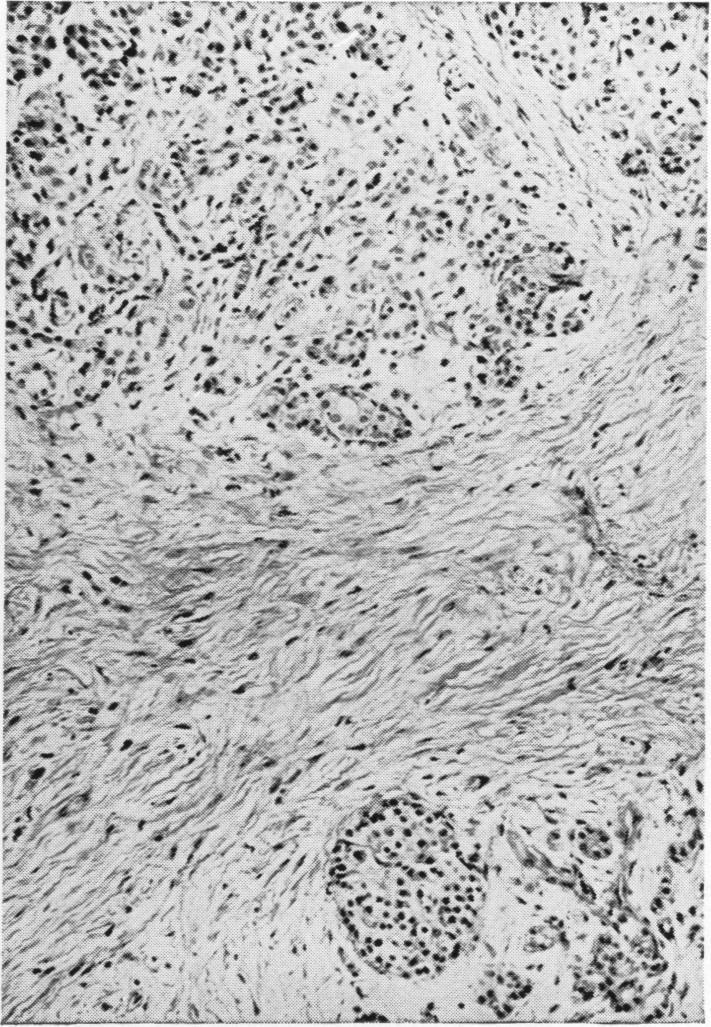

Chronic relapsing pancreatitis; treatment by subtotal gastrectomy and vagotomy.

Ann Surg. 1950 Feb;131(2):145-58, illust. doi: 10.1097/00000658-195002000-00002.